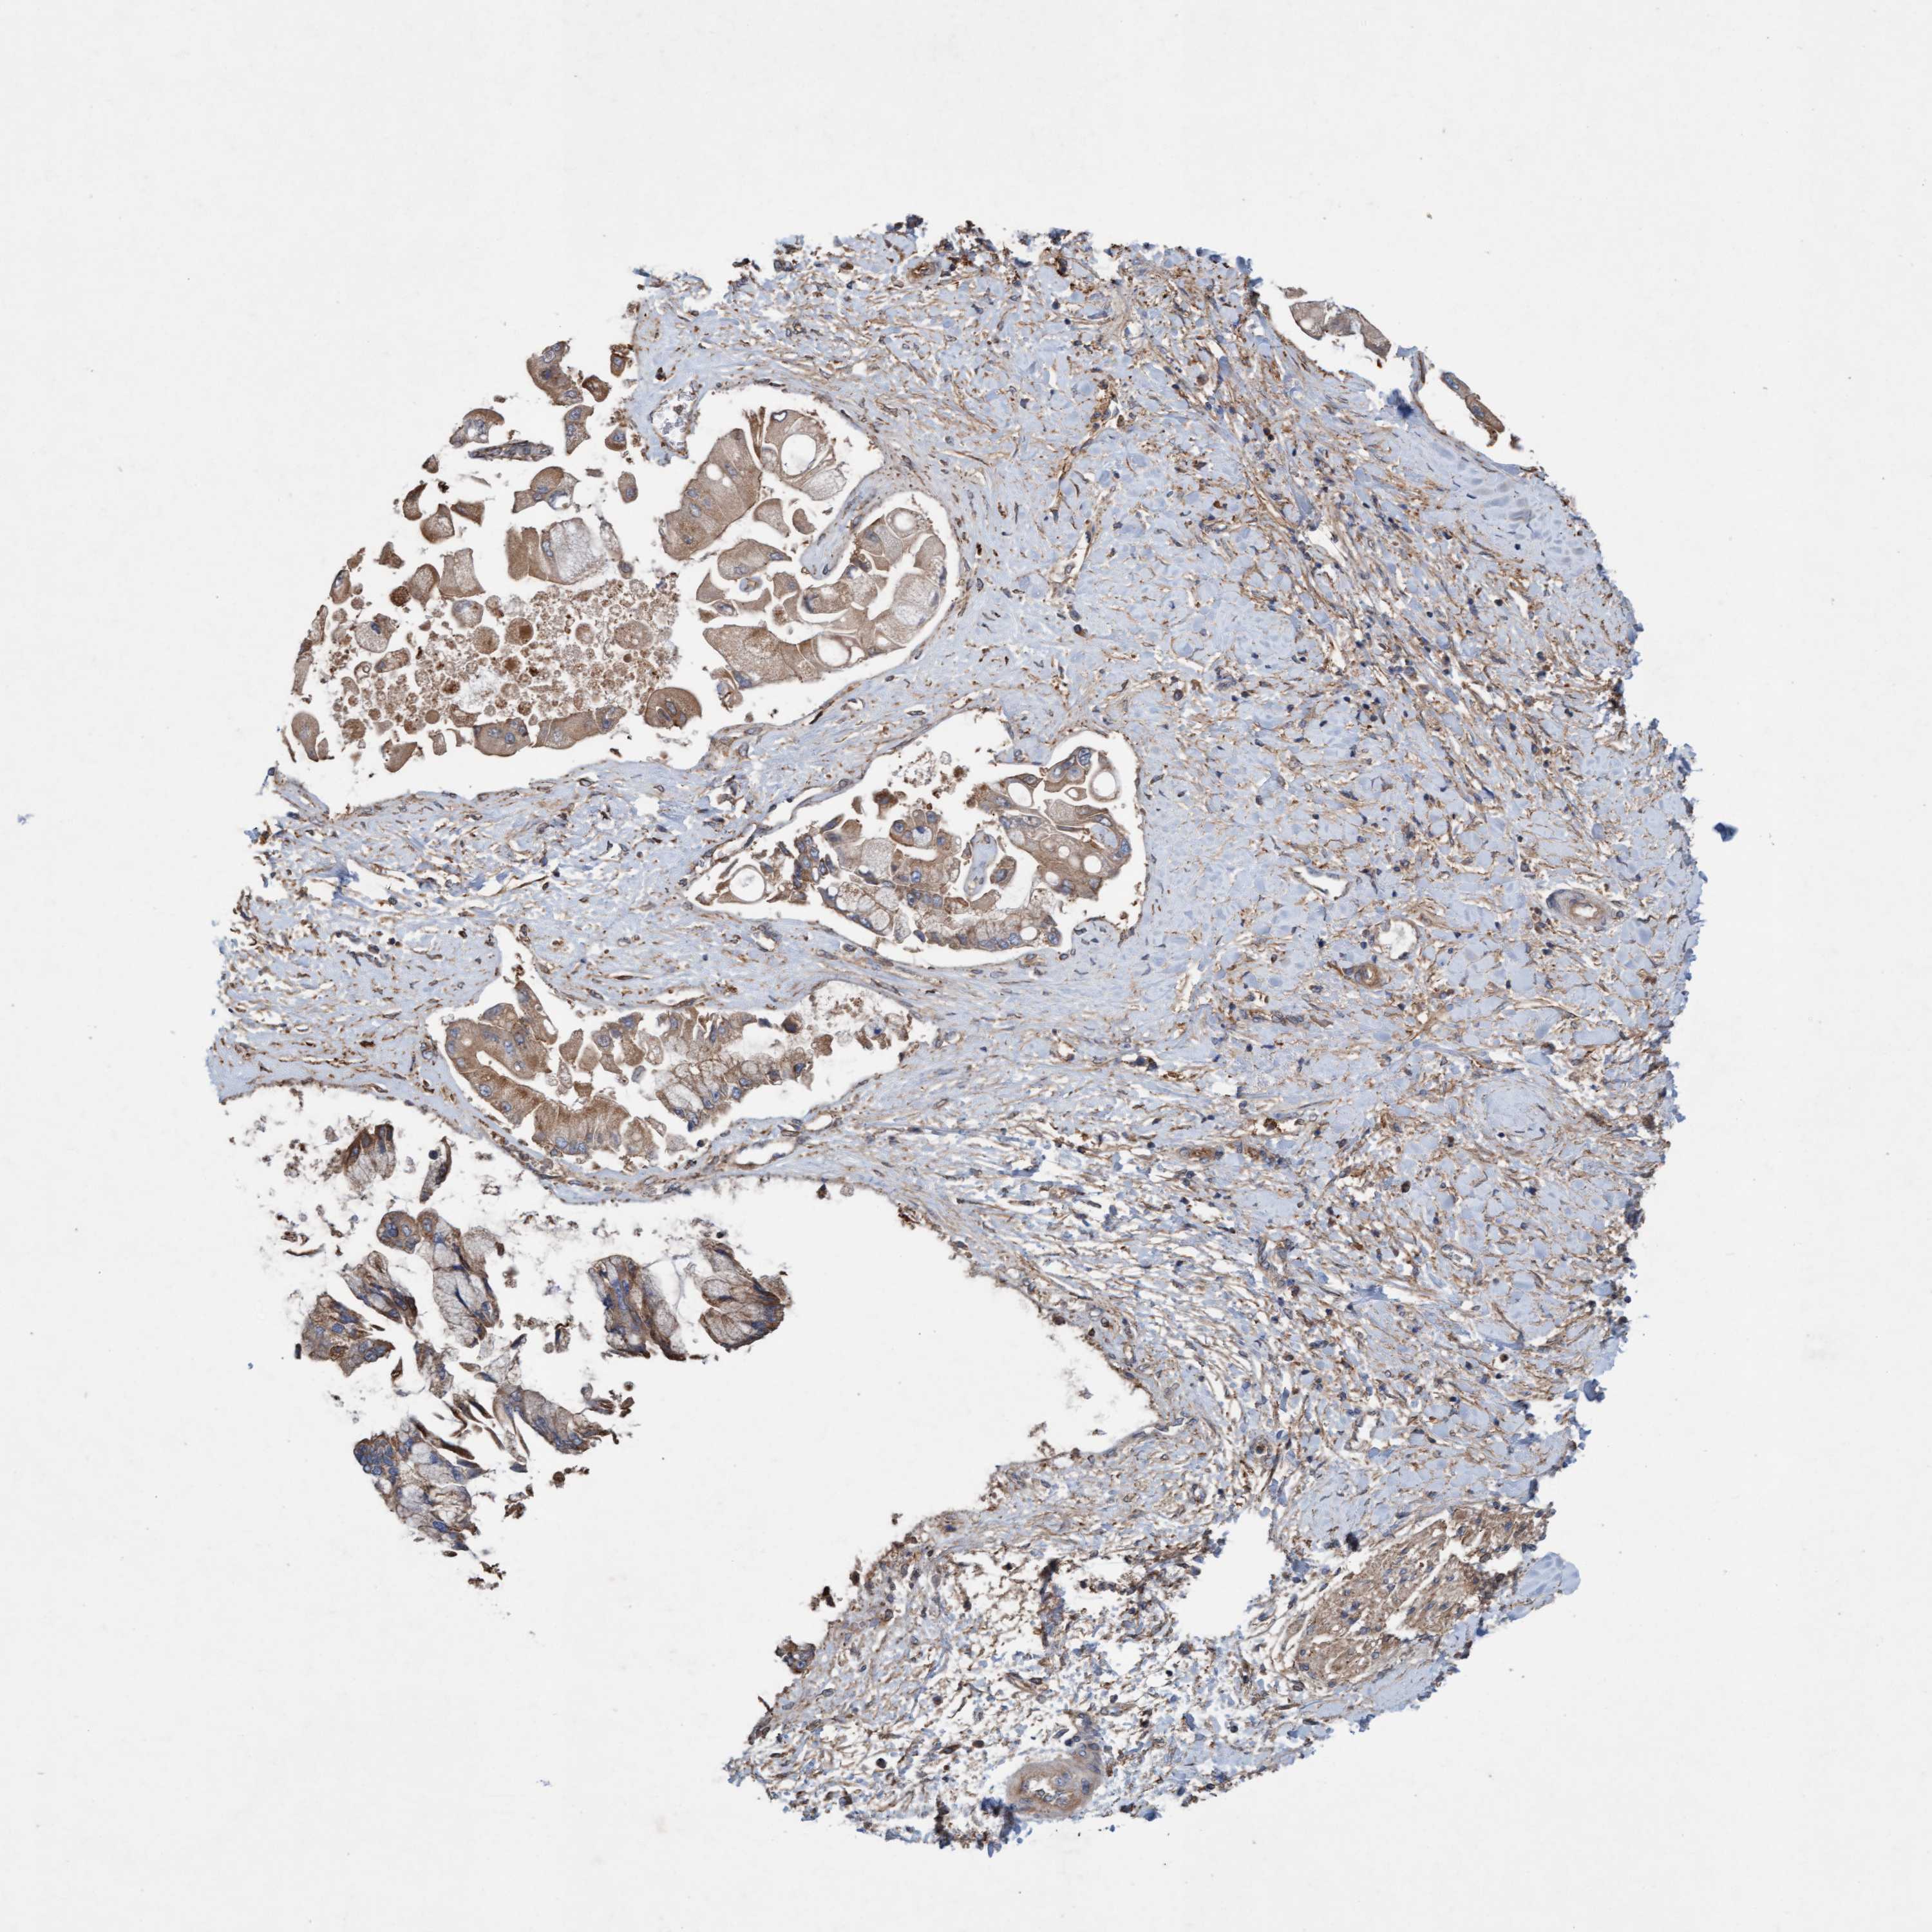

LIVER CANCER - Protein expressioni

A mouse-over function shows sample information and annotation data. Click on an image to view it in a full screen mode. Samples can be filtered based on level of antibody staining by selecting one or several of the following categories: high, medium, low and not detected. The assay and annotation is described here.

Note that samples used for immunohistochemistry by the Human Protein Atlas do not correspond to samples in the TCGA dataset.

Antibody stainingi

Antibody staining in the annotated cell types in the current human tissue is reported as not detected, low, medium, or high, based on conventional immunohistochemistry profiling in selected tissues. This score is based on the combination of the staining intensity and fraction of stained cells.

Each image is clickable and will lead to virtual microscopy that enables deeper exploration of all samples and also displays staining intensity scores, fraction scores and subcellular localization as well as patient and tissue information for each sample.

Antibody HPA021425

Antibody HPA024423

Staining

High

Medium

Low

Not detected

Intensity

Strong

Moderate

Weak

Negative

Quantity

>75%

75%-25%

<25%

None

Location

Nuclear

Cytoplasmic/membranous

Cytoplasmic/membranous,nuclear

Cholangiocarcinoma

Carcinoma, Hepatocellular, NOS